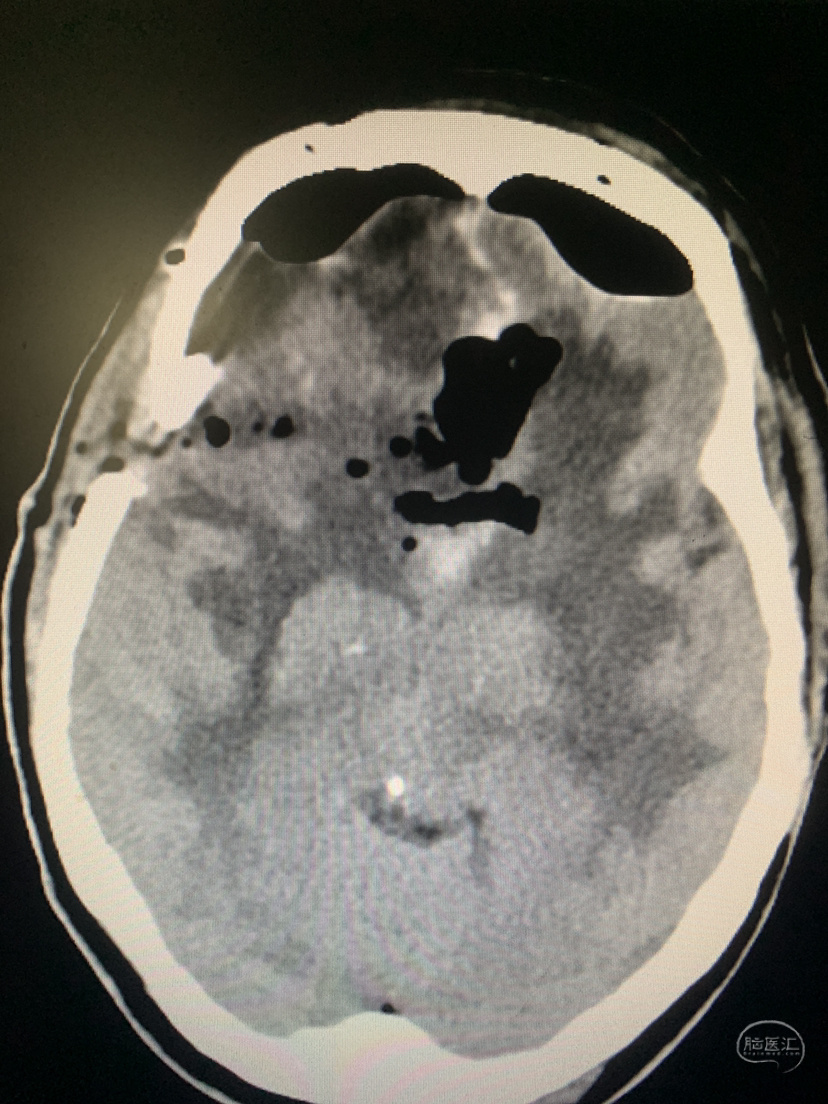

术前CT

术后CT